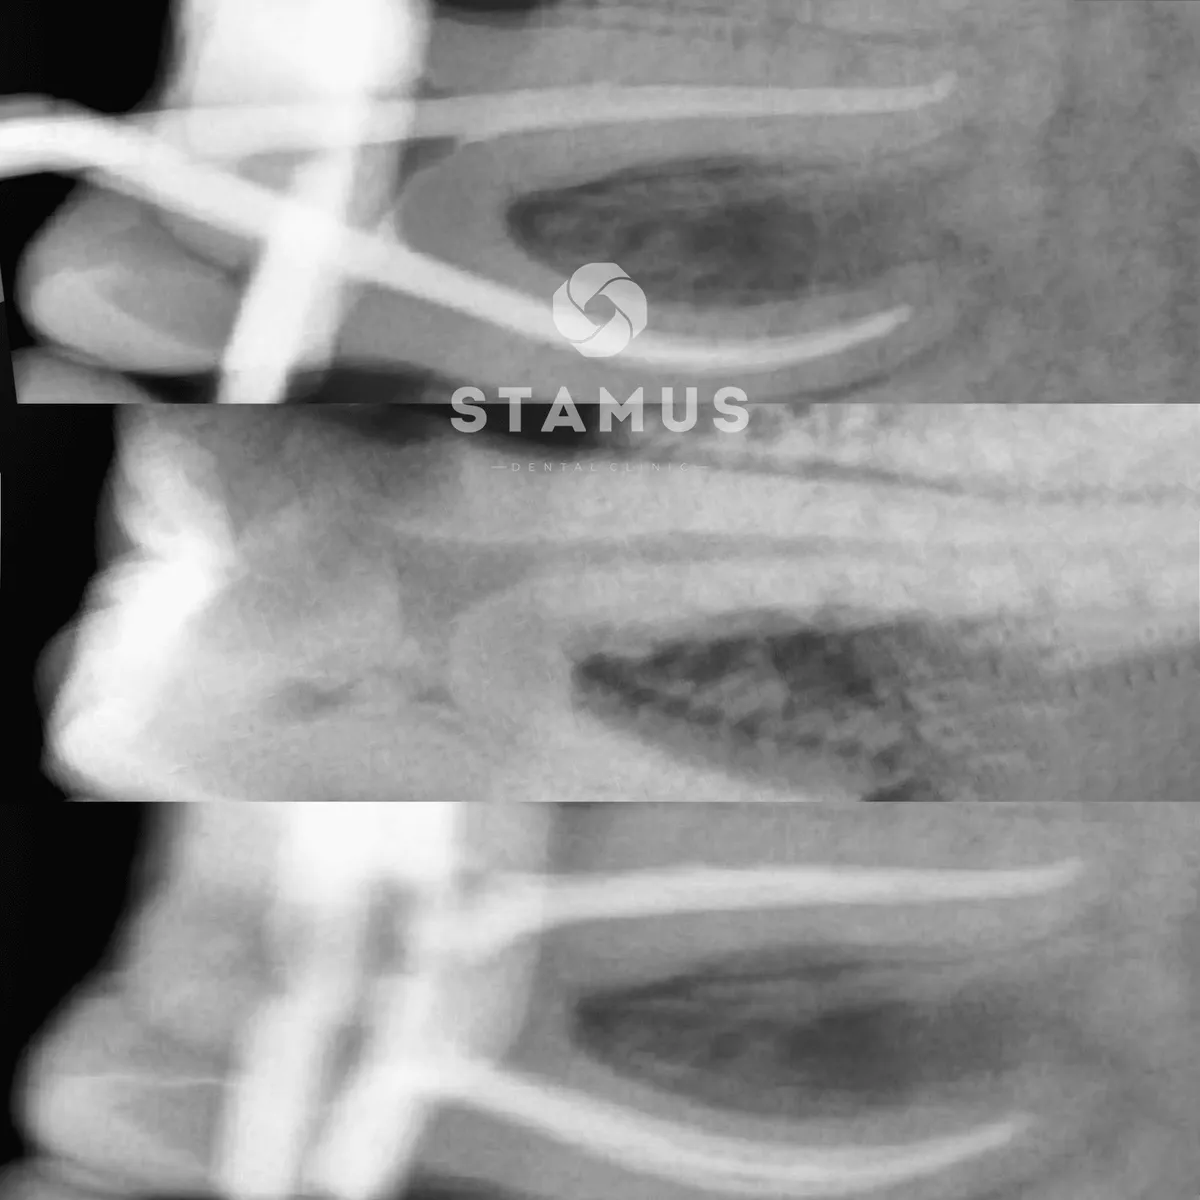

Лечение периодонтита

Проведено эндодонтическое лечение и вскрытие абсцесса за 2 посещения. Рекомендовано покрытие зуб коронкой